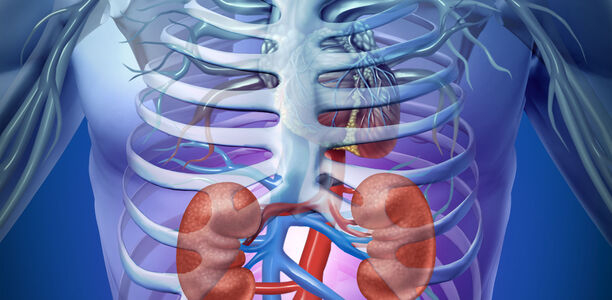

Beneficial renal effect of insulin glargine 300 U/ml initiation in type 2 diabetes mellitus patients previously treated with insulin

© freshidea - Fotolia